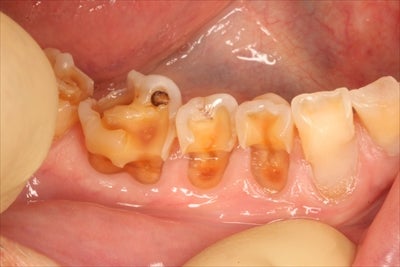

衝撃画像じゃないですか!?

ムシ歯ではないんですよ!!

「酸蝕歯」とは

酸性の食べ物(柑橘類、酢、炭酸等)によって

歯の表面=エナメル質が溶けた歯のことです。